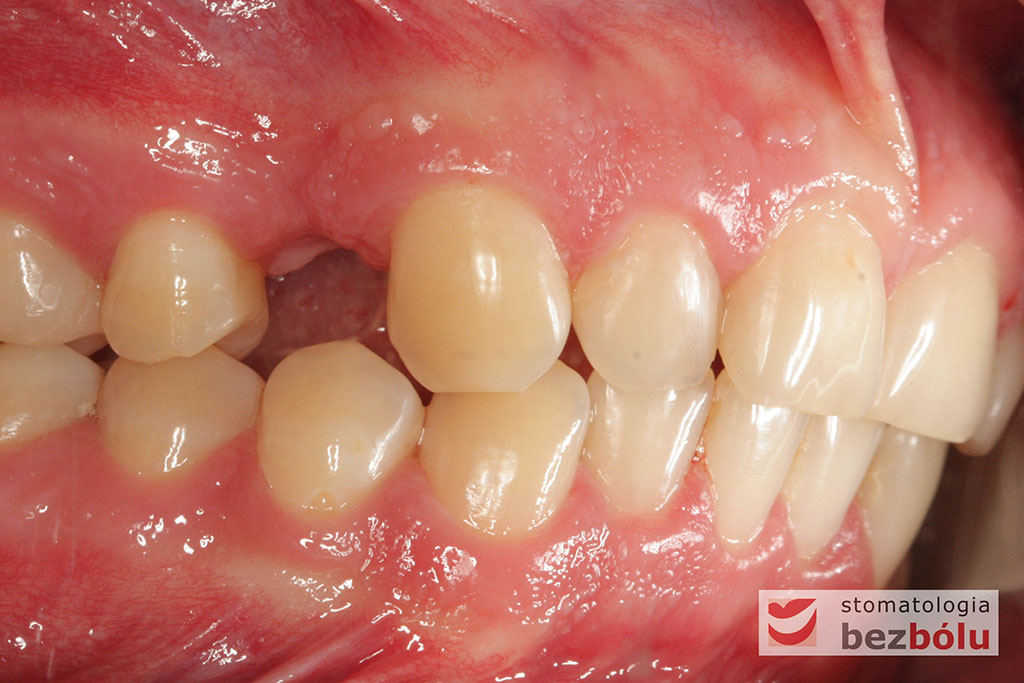

Młody pacjent w wieku lat 28 po wstępnym rozpoznaniu, ze zdiagnozowanym złamaniem kła zarówno górnego jak i dolnego, został skierowany na terapię implantoprotetyczną, prowadzoną przez lekarza dentystę Marcina. W świetle braku możliwości wykonania ekstruzji ortodontycznej i zachowawczego podejścia do leczenia, podjęto decyzję o usunięciu obu zębów, zastosowaniu ułatwiającej gojenie procedury A-PRF i przygotowaniu pacjenta do zabiegu implantologicznego, dodatkowo uzupełnionego o wprowadzenia implantu w miejscu braku zębowego w pEdytujozycji pierwszego przedtrzonowca w szczęce po stronie prawej.

Procedurę chirurgiczną rozpoczęto od sprawdzenia przylegania szablonów do zębów pacjenta oraz znieczulenia miejscowego. W kolejnym kroku, przy pomocy specjalnie przeznaczonego do tego celu zestawu wierteł, wypreparowano krążki dziąsła punktowo odsłaniające kość a następnie poprzez tuleje prowadzące, z najwyższą precyzją, opracowano łoże implantu. Kulminacyjny moment zabiegu, czyli wprowadzenie wszczepów MIS C1 również odbyło się poprzez szablon, gwarantując precyzyjną lokalizację implantów. Zwieńczeniem całej procedury było przyszycie uprzednio wypreparowanych krążków śluzówkowo-okostnowych. Tuż po zabiegu, celem weryfikacji poprawnej pozycji implantów, wykonano zdjęcie ortopantomograficzne. Podczas wizyt kontrolnych, pacjent nie skarżył się na żadne dolegliwości bólowe, nie wystąpił obrzęk, a zreponowane we właściwych miejscach fragmenty dziąsła nie wykazywały oznak martwicy, co świadczyło o ich ponownym ukrwieniu i wgojeniu się. Wszystkie te przesłanki jasno wskazują na skuteczność zastosowania techniki komputerowej nawigacji w implantologii.